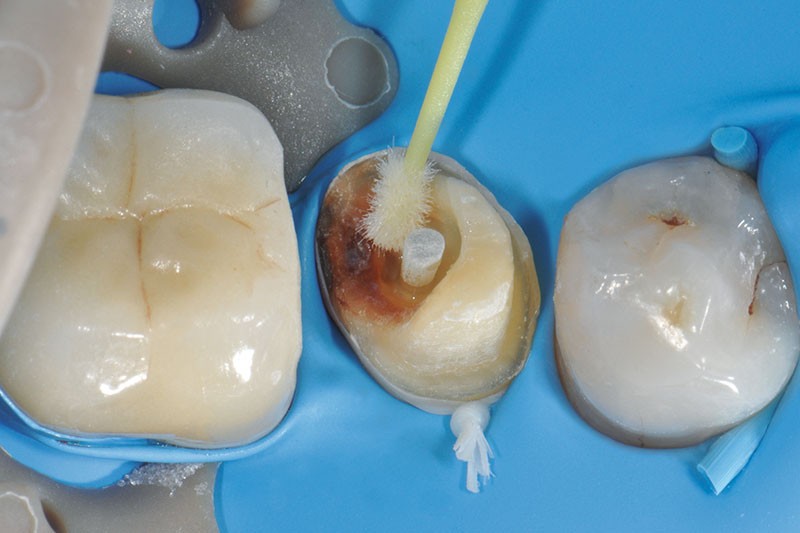

13, 14. Le canal radiculaire est nettoyé à l’aide de chlorhexidine à 2% et soigneusement rincé à l’eau avant d’être séché avec des pointes de papier.